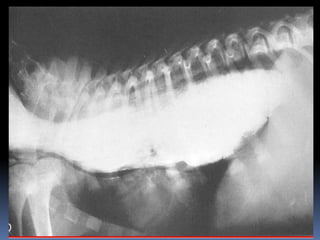

Me saca la piedra

Me saca lapiedra